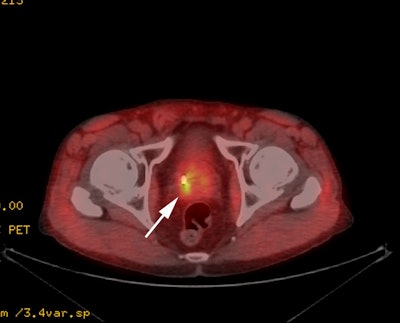

|

18F-Fluciclovine for

biochemical recurrence: The patient below had

undergone prior external XRT for treatment of prostate

cancer and had suspicion for biochemical recurrence based

on slowly rising PSA. The exam demonstrated focal uptake

in the right prostate adjacent to an internal fudicial

marker. The finding is seen on both AC (second image) and

non-AC images (third image) which confirms the finding is

not an artifact related to the beam hardening associated

with the marker. The referring physician elected not to

pursue the exam finding and was primarily concerned with

the presence of nodal disease which was not evident on the

study. |